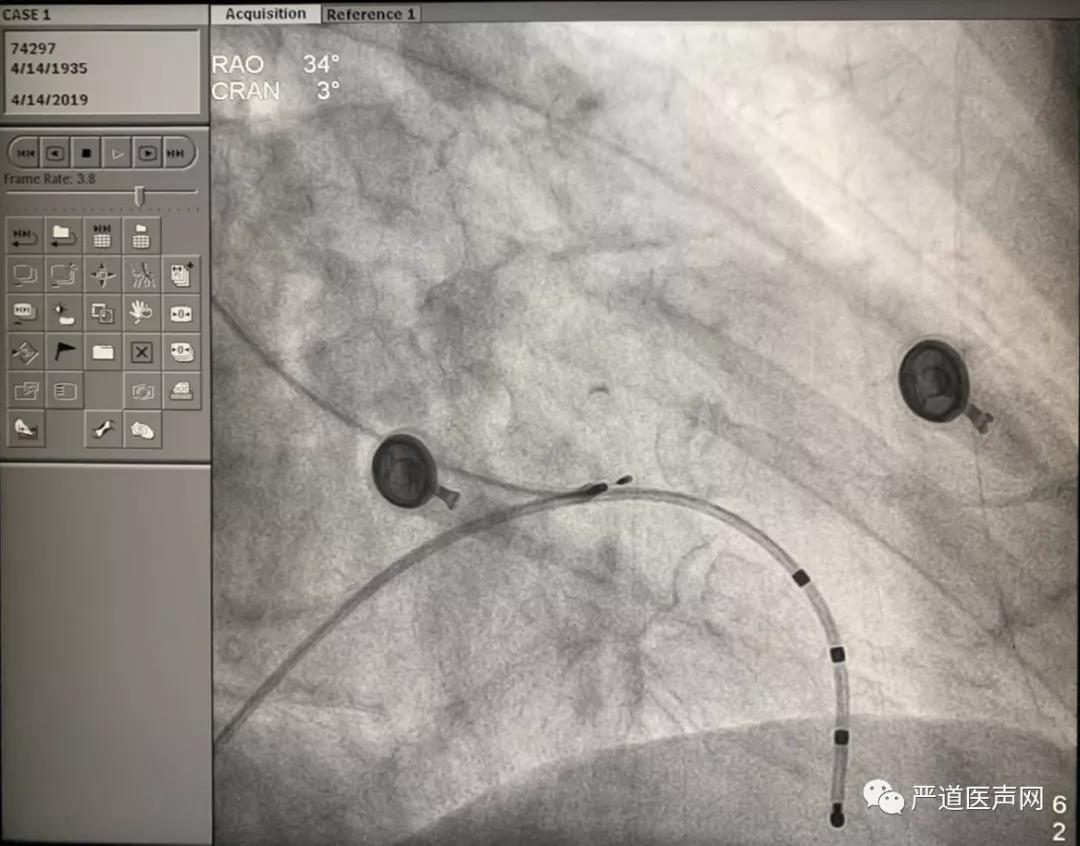

Case 4 囊袋感染破溃电极拔除后右侧新植入希氏束起搏电极,远端希氏束起搏,阈值0.6V